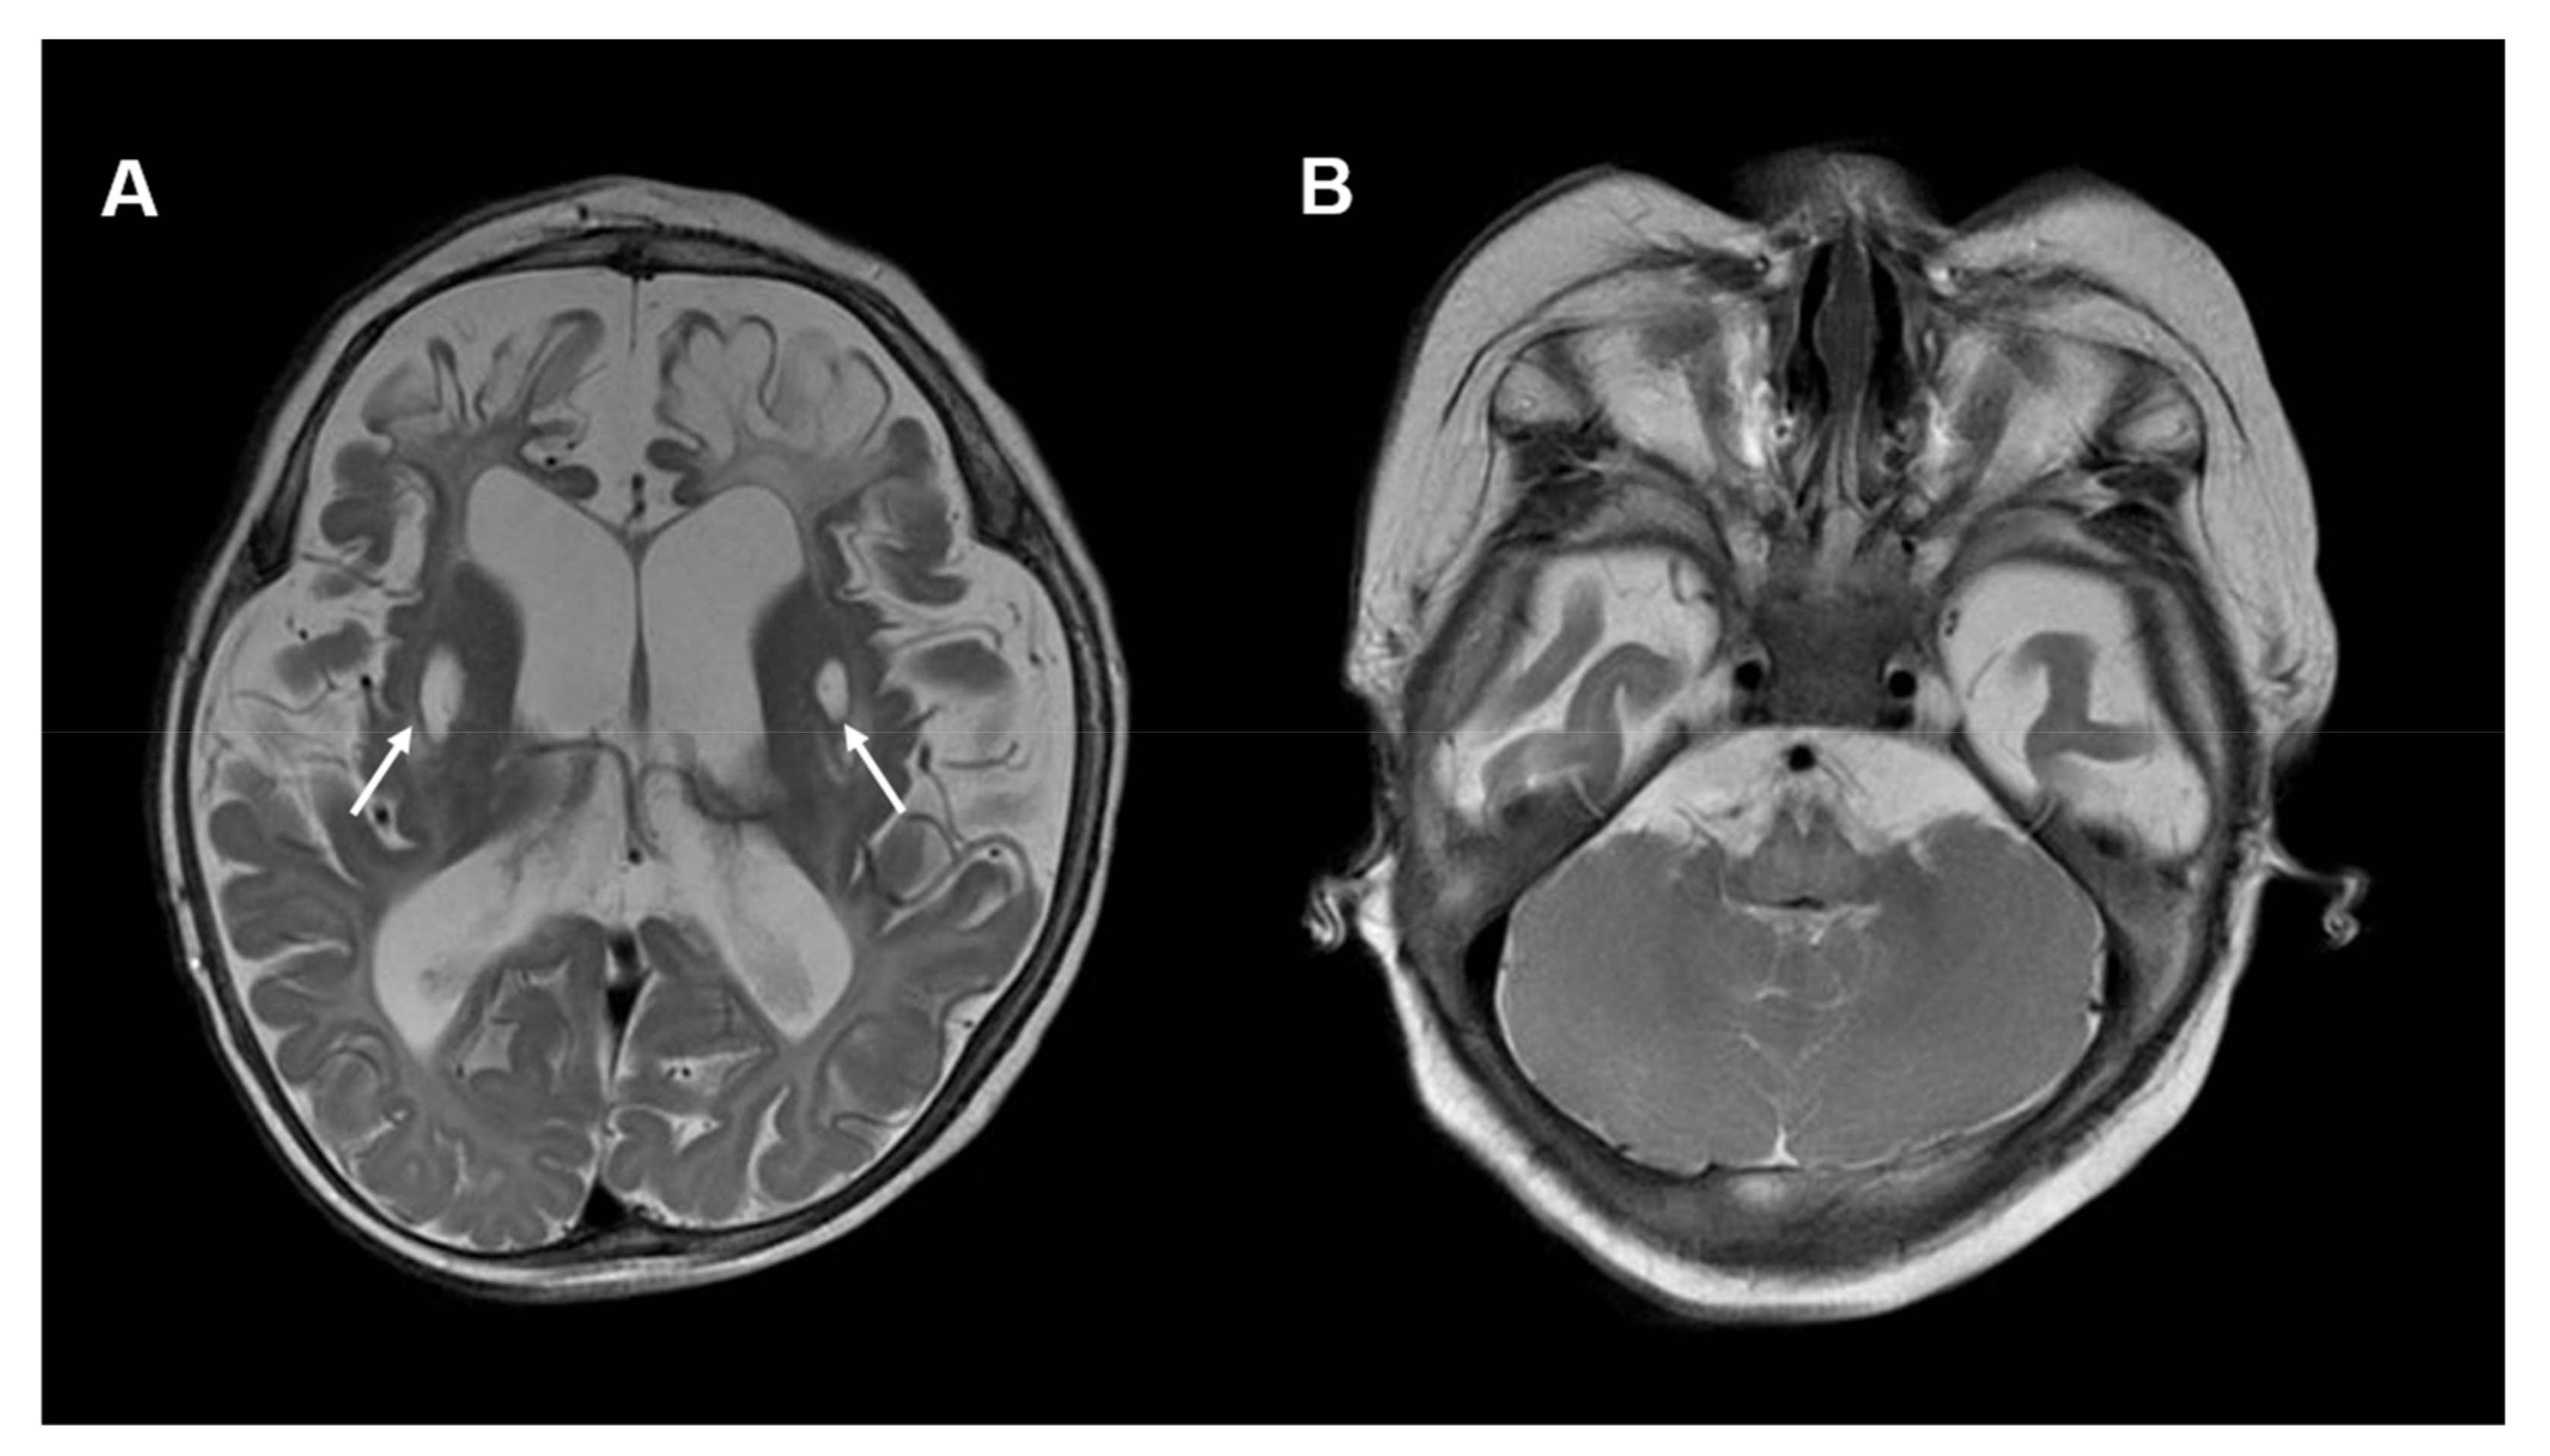

An example of imaging findings in COQ7 deficiency is depicted in Figure 4.

Figure 4.

Neuroimaging in COQ7 deficiency: (A) Brain MRI, T2-weighted, axial images of a 10-month-old boy with COQ7 deficiency. The MRI shows global brain atrophy and areas of encephalomalacia in bilateral frontal lobes. In addition, symmetric cystic changes within the putamen are visible (white arrows). (B) No cerebellar abnormalities are visible. Other MRI images of this individual were published previously [41].

Kwong et al. reported the case of a neonate with “encephalo-myo-nephro-cardiopathy”. Brain MRI at the age of 10 months showed multiple T2-hyperintense cystic changes involving bilateral corona radiata, basal ganglia and thalami as well as frontal cerebral atrophy. MR spectroscopy showed a lactate peak [41]. A nine-year-old girl with neurological symptoms and COQ7 deficiency referred to by Hashemi et al. showed no gross abnormalities in MRI of the brain and spine [24].